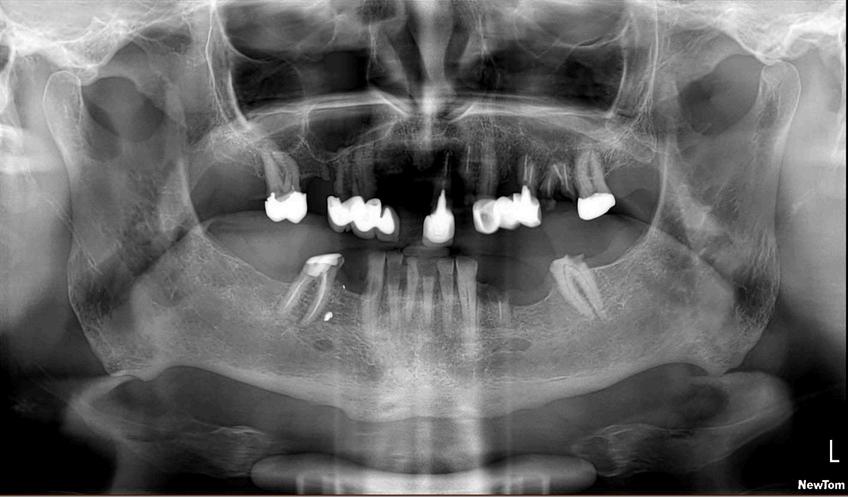

ฟนและกระดกขากรรไกรมหลายสวนทซอนอยใตเหงอก และเมอ เกดความผดปกตขนอาจจะไมสามารถมองเหนไดเพยงจากการ

การสงถายภาพรงส เพอการวนจฉยโรคในชองปากมความสาคญอยางยง

โดยเฉพาะในการประเมนรอยผของฟน ในผปวยทไมเคย ตรวจสขภาพชองปากมากอนหรอผทมาพบทนตแพทย เป นครงแรก

นอกเหนอจากการตรวจรอยผในชองปากจากการตรวจด

โดยตรงแลว ทนตแพทยจะพจารณาการถายภาพรงสใน

ชองปาก เพอชวยตรวจหาบรเวณรอยผดานประชดฟน (proximal caries)